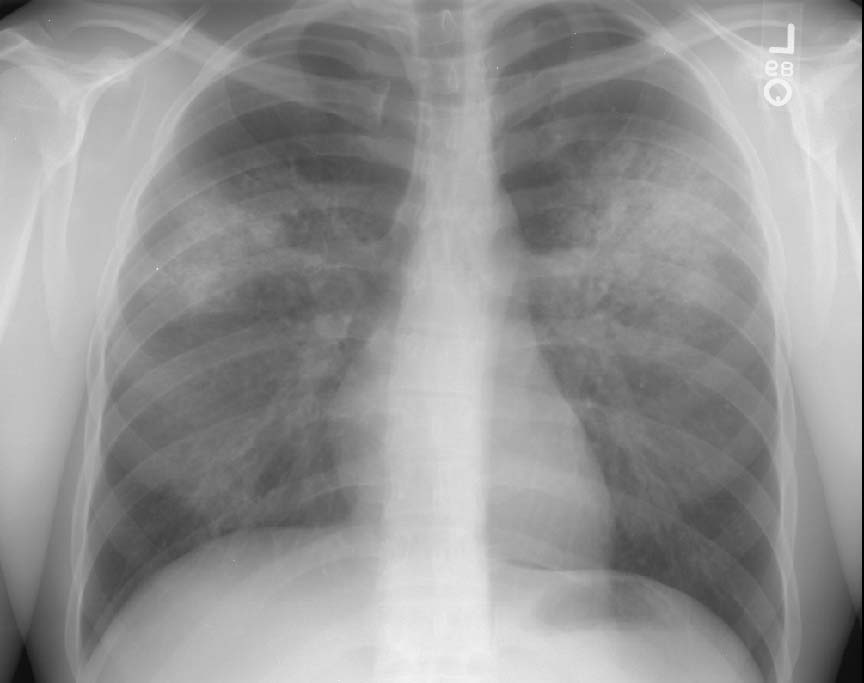

Scott WilliamsAutoimmuneAutoimmune > Sarcoid > Images > Sarcoid3April 2, 2002Central Nervous SystemCNS > CSF imagingApril 2, 2002PETPET Myocardial ImagingApril 2, 2002CardiacCardiac > Adultdz > ProstheticApril 2, 2002Pulmonary ImagingGeneral > BiopsyApril 2, 2002AutoimmuneAutoimmune > Wegener > Images > Case1April 2, 2002Vascular AbnormalitiesVascular > PE > Images > Iliac DVTApril 2, 2002GastrointentinalGastrointestinal > Hepatobiliary > Biliary atresiaApril 2, 2002AutoimmuneAutoimmune > FollbronchApril 2, 2002AutoimmuneAutoimmune > EGApril 2, 2002Previous PagePage 108 of 265Next PageTop StoriesCT5-year CTC screening interval is appropriate for colorectal cancerThe study's findings add to an ongoing conversation about the use of CTC for colorectal cancer screening.MRIASTRO: Daily MRgRT recontouring improves prostate treatment outcomesRadiation Oncology/TherapyASTRO: Radiation therapy comparable to surgery for early-stage lung cancerCTCT use in the ED has more than doubled over a decadeSponsor ContentDigital Innovations Shaping the Future of Radiology